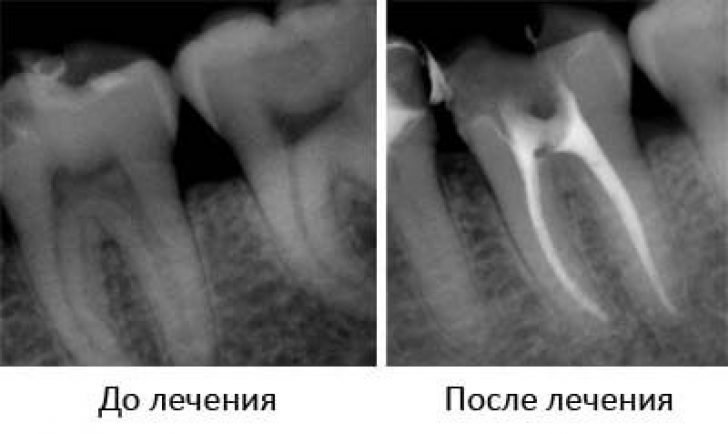

Проведение рентгенографии после терапии

Рентген является не только методом диагностики патологии, но и выступает в качестве контроля над эффективностью терапии. Посредством исследования врач определяет:

- Качество удаления пульпы. Неполное удаление приводит к повторному воспалению.

- Характер каналов зуба, их физиологическое строение и глубину.

- Насколько качественно были запломбированы каналы с использованием медицинского цемента или гуттаперчи. В случае недостаточной пломбировки или избытка пломбировочного материала в каналах, лечение зуба проводится повторно.